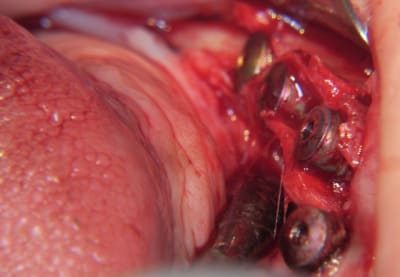

ou comme ça encore...

( agénésie de 12 - expansion osseuse sur une crête fine ) agénésie...

la suite à Sallanches les 2 et 3 Février pour ceux qui veulent encore s’inscrire)